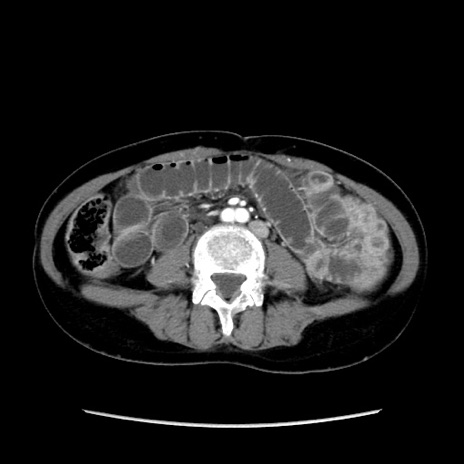

症例32(横断像)

【症例】40歳代 女性

【主訴】上腹部痛、嘔気・嘔吐

【現病歴】約9時間前頃から急に上腹部痛、嘔気、嘔吐が出現。改善しないため救急要請。

【既往歴】子宮頚癌(広汎子宮全摘術、放射線療法)、腸閉塞

【身体所見】腹部:平坦、軟、腸雑音亢進、上腹部を中心に腹部全体に圧痛あり。

【データ】WBC 8400、CRP 0.03